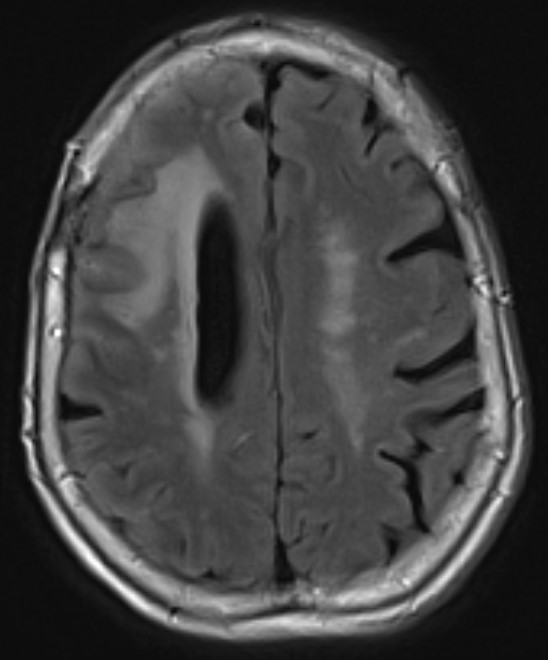

A 79-year-old right handed woman presented to a local hospital with left hemiparesis affecting her upper and lower extremities with mild left facial weakness for the last 2 weeks. She had a longstanding history of RA and had been off immune suppressant therapy for a few months due to improvement in symptoms. She had previously been on methotrexate and adalimumab in the past. She was evaluated with imaging and lumbar puncture (LP) at the time. MRI brain showed a semi-enhancing lesion over the right frontal lobe near the motor cortex with meningeal enhancement (Figure 1). CSF studies showed elevated protein at 65 and pleocytosis with WBC count of 47, 80% lymphocytes. CSF infectious panel was negative, but serum HSV-1 was positive. She reported a cold sore around this time as well. She was treated with broad spectrum antibiotics and acyclovir for 2 weeks. Infectious workup was otherwise negative. She did not have much improvement in her symptoms and was presented to our hospital 3 weeks later. Repeat CSF evaluation showed protein of 70 along with pleocytosis of 33 white blood cell (WBC), 75% lymphocytes. She received treatment with extended broad-spectrum antibiotics for 2 weeks. Rheumatological evaluation was negative for other signs of active RA. EEG showed bitemporal slowing with some quasi-periodic activity over the right temporal regions. She had some left arm shaking as well and was placed on levetiracetam for seizure prophylaxis. She did not have much improvement in her symptoms. A brain biopsy was performed which showed histopathological findings consistent with granulomatous inflammation confirming a diagnosis of RM (Figures 2-4). Labs showed highly elevated rheumatoid factor (RF) (>320) and anti-cyclinolytic citrullinated peptide (CCP) antibodies (>250). Rheumatology was consulted again and recommended high dose therapy with intravenous methylprednisolone for 5 days followed by resumption of immune modulating therapy. She developed a small right frontal ischemic stroke as a resultant of vasculitis from RM which caused exacerbation of left lower extremity weakness (Figure 5). She is kept on aspirin 81 mg daily for maintenance therapy for stroke prevention and levetiracetam for seizure prophylaxis along with daily prednisone and rituximab maintenance therapy for management of her RA / RM from rheumatology. She continues to work with physical therapy for her left hemiparesis which has shown some improvement. She sees rheumatology and neurology for continued follow up.

Figure 1. MRI brain showing right frontal lesion with cerebral edema and meningeal involvement.